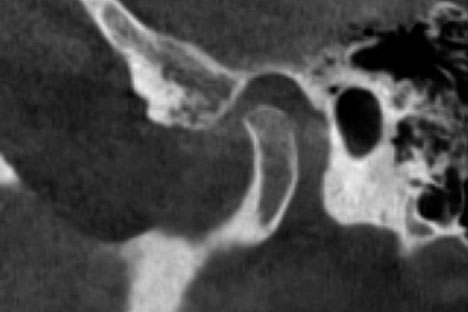

После лечения проанализировано положение головок нижней челюсти в суставных впадинах по данным КТ ВНЧС (рис. 27).

Рис. 27. Компьютерная томограмма височно-нижнечелюстного сустава после лечения: а — правый; b — левый

Fig. 27. Computed tomography scan of the temporomandibular joint after treatment: а, right; b, left